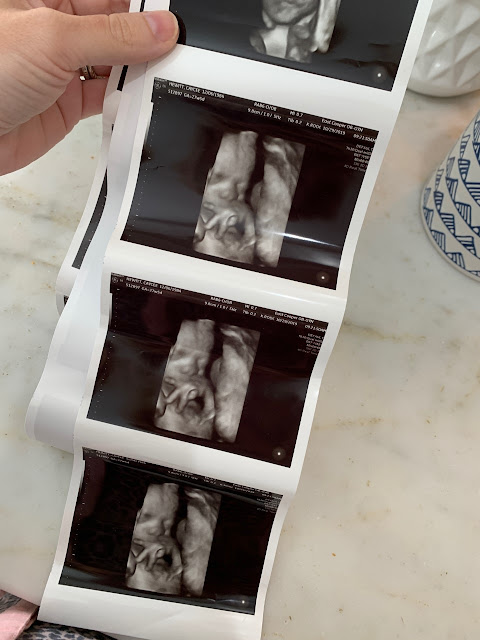

We had another ultrasound this week and it was so exciting to get to see our sweet baby girl in my belly. Todd and I are both very excited and so ready for January!!

FOUR //

Speaking of being ready for January, at our appointment we had to make a game plan for her birth. As most of you know, I had to have a c-section with both Carson and Taylor, but this time I’ve been given the go-ahead to try and attempt a v-back. At this point, my percentage is looking pretty good for it being a success, but we really won’t know anything for sure until right before her due date. That being said, if any of you are comfortable sharing, I would LOVE to hear from any of you that have had a successful (or unsuccessful) v-back and what your experience was like.